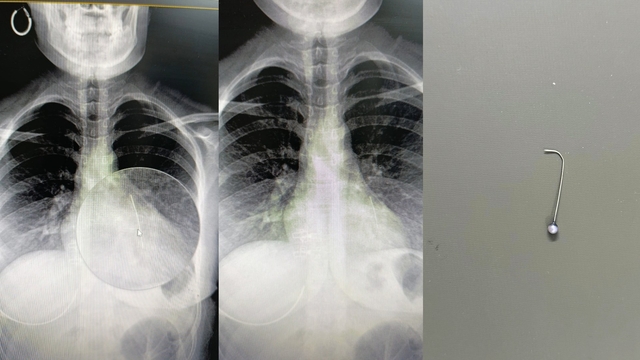

ŞANLIURFA’da, yuttuğu toplu iğnenin akciğerine saplanması sonucu komaya giren Bedia Özbay (16), yapılan ameliyatla sağlığına kavuştu.

Olay, Günbalı Mahallesi’nde meydana geldi. Evden dışarı çıkmaya hazırlanan Bedia Özbay, eşarbını düzeltmek isterken ağzında tuttuğu toplu iğneyi yuttu. Nefes almakta zorlanan Özbay, ailesi tarafından Mehmet Akif İnan Eğitim ve Araştırma Hastanesi’ne götürüldü. Yapılan tetkiklerde iğnenin Özbay'ın sol akciğerine saplandığı tespit edildi. Hayati tehlikesi bulunan Bedia Özbay, Op. Dr. Mehmet Emin Balcıoğlu tarafından ameliyata alındı. Balcıoğlu, bronkoskopi yöntemiyle sol akciğerdeki iğneyi operasyonla çıkardı. Yaklaşık bir saat süren ameliyatın ardından Özbay’ın hayati tehlikeyi atlattığı belirtildi.

Op. Dr. Balcıoğlu, operasyon sonrası yaptığı açıklamada, “16 yaşındaki hastamız, öğle saatlerinde başörtüsünü düzeltirken toplu iğneyi yutmuş. Öğlenden beri Şanlıurfa Devlet Hastanesi’nde bekliyormuş. Şanlıurfa ve çevre illerdeki hastaneler hastayı kabul etmemiş. Bronkoskopi yöntemiyle sol akciğerin alt kısmına yerleşmiş iğneyi çok şükür başarıyla çıkardık. Hastamızın durumu iyi, birkaç gün misafir ettikten sonra sağlıklı şekilde evine göndereceğiz” dedi.